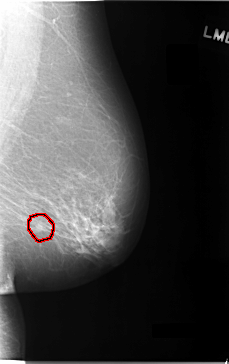

C_0027_1.LEFT_MLO

LEFT_MLO LINES 5824 PIXELS_PER_LINE 3656 BITS_PER_PIXEL 12 RESOLUTION 50 OVERLAY

FILE: C_0027_1.LEFT_MLO.OVERLAY

TOTAL_ABNORMALITIES 1

ABNORMALITY 1

LESION_TYPE MASS SHAPE OVAL MARGINS ILL_DEFINED

ASSESSMENT 5

SUBTLETY 2

PATHOLOGY MALIGNANT

TOTAL_OUTLINES 1

BOUNDARY